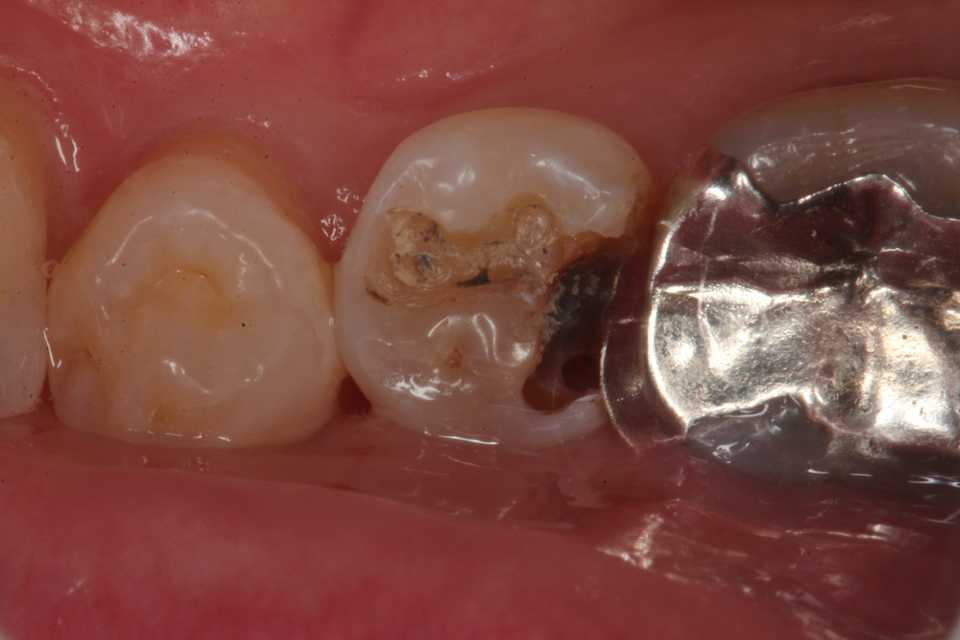

50代女性、右下5、インレー2次カリエス

1mmのマージンより内側は虫歯が残っていても差し支えない。虫歯(軟化象牙質)はα-TCPで再硬化して治るからだ。

では時系列でどうぞ